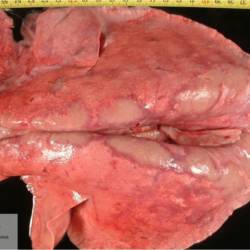

Pàgina anterior de 637 Pàgina següent 3181 total Ovine Specie: Ovine Organ: Lung Lesion: Pneumonia Lesion modifier: Pneumonia - Embolic Disease: - Files/Expedient: Leon6 Position: 253 (1 views) Ovine Specie: Ovine Organ: Lung Lesion: Pneumonia Lesion modifier: Pneumonia - Embolic Disease: - Files/Expedient: Leon6 Position: 136 (2 views) Ovine Specie: Ovine Organ: Liver Lesion: Omphalophlebitis Lesion modifier: Omphalophlebitis - Purulent Disease: - Not viewed Ovine Specie: Ovine Organ: Lung Lesion: Pneumonia Lesion modifier: Pneumonia - Verminous Disease: - Position: 253 (1 views) Bovine Specie: Bovine Organ: Oral cavity Lesion: Stomatitis Lesion modifier: Stomatitis - Erosive Disease: Bovine viral diarrhea Not viewed Pàgina anterior de 637 Pàgina següent Títol Select...Avian (Exotic) (110)Avian (Poultry) (76)Bovine (317)Canine (935)Caprine (47)Equine (257)Feline (326)Ferret (19)General (127)Marine mammal (22)Non-human primate (20)Ovine (328)Porcine (379)Rabbit (61)Reptile (38)Rodent (28)Wildlife (91) Format Select...- (60)Abomasum (37)Adrenal gland (10)Blood (7)Blood vessel (50)Body as a whole (19)Bone (57)Bone marrow (21)Brain (93)Cloaca (1)Diaphragm (2)Ear (5)Esophagus (39)Eye (16)Fetus (12)Gallbladder (23)Gizzard (2)Heart (265)Intestine (356)Joint (32)Kidney (443)Larynx (5)Liver (326)Lung (264)Lymph node (91)Mammary gland (10)Mediastinum (1)Muscle (22)Nasal cavity (22)Nerve (7)Omasum (5)Oral cavity (63)Ovary (14)Oviduct (8)Pancreas (7)Parathyroid (5)Penis (10)Peritoneum (65)Pharynx (9)Pituitary gland (6)Placenta (7)Prostate (8)Proventriculus (3)Reticulum (1)Rumen (28)Sinus (7)Skin (181)Spinal cord (15)Spleen (105)Stomach (125)Teeth (1)Testicle (11)Thoracic cavity (31)Thymus (13)Thyroid gland (5)Tongue (32)Tonsils (11)Trachea (11)Urethra (5)Urinay bladder (61)Uterus (27)Vagina (1)Vulva (1)Yolk sac (1) Cobertura Select...- (152)Abomasitis (26)Abscess (27)Acidosis (1)Adenocarcinoma (20)Adenoma (9)Aerosacculitis (6)Agenesis (1)Agnathia (1)Alopecia (7)Amyloidosis (12)Aneurysm (6)Angiectasis (1)Anthracosis (1)Arteritis (11)Arthritis (15)Arthrogryposis (6)Artifact (4)Ascites (13)Atelectasis (8)Atherosclerosis (5)Atresia (1)Atrial septal defect (2)Atrophy (10)Autolysis (7)Bronchitis (6)Bronchopneumonia (26)Cachexia (2)Carcinoma (103)Cardiomyopathy (19)Cellulitis (2)Chemodectoma (4)Cholangiohepatitis (4)Cholangitis (19)Cholecystitis (4)Cholestasis (5)Chondrodysplasia (2)Chondrosarcoma (2)Chronic passive congestion (13)Chylothorax (2)Cirrhosis (6)Coelomitis (3)Coenurus cerebralis (4)Colitis (40)Congestion (17)Conjunctivitis (5)Coronitis (3)Cryptorchidism (3)Cyst (25)Cystitis (24)Dermatitis (69)Diaphragmatic hernia (4)Dilation (28)Discospondylitis (1)Disseminated intravascular coagulation (7)Dyschondroplasia (1)Dysplasia (29)Ectopia cordis (1)Ectopic ureter (1)Edema (55)Emphysema (5)Encephalitis (5)Endocardiosis (14)Endocarditis (26)Endometritis (5)Enteritis (118)Enterolith (6)Epulis (3)Esophagitis (14)Fasciitis (1)Fibrosis (7)Fibrous osteodystrophy (8)Fistula (1)Folliculitis (3)Fracture (2)Gastritis (34)Gingivitis (5)Glioma (8)Glomerulonephritis (21)Glossitis (25)Glycogenosis (1)Gout (8)Granuloma (2)Granulosa cell tumor (4)Hemangioma (9)Hemangiosarcoma (46)Hematoma (8)Hemoglobinuria (2)Hemopericardium (12)Hemoperitoneum (2)Hemorrhage (100)Hemosiderosis (7)Hemothorax (2)Hepatitis (78)Hernia (11)Histiocytosis (3)Hydatid cyst (11)Hydrocephalus (9)Hydrometra (1)Hydronephrosis (22)Hydropericardium (6)Hydrothorax (3)Hydroureter (5)Hyperkeratosis (8)Hyperostosis (4)Hyperplasia (37)Hypertrophy (9)Hypopigmentation (1)Hypoplasia (7)Hypopyon (1)Impaction (6)Infarction (63)Insulinoma (6)Intussusception (5)Jaundice (17)Laminitis (2)Laryngitis (2)Leiomyoma (5)Leukemia (13)Lipidosis (36)Lipoma (7)Lymphadenitis (45)Lymphadenopathy (7)Lymphangiectasia (6)Lymphangitis (5)Lymphoma (221)Malacia (11)Malignant melanoma (15)Mast cell tumor (11)Mastitis (8)Megaesophagus (2)Melanosis (3)Melena (4)Meningioma (6)Meningitis (6)Meningocele (2)Meningoencephalitis (5)Mesothelioma (5)Methemoglobinemia (2)Mineralization (10)Mucocele (5)Mucometra (1)Multilobular bone tumor (1)Mummification (3)Myelofibrosis (1)Myocarditis (4)Myositis (5)Necrosis (81)Nephritis (113)Nephroblastoma (6)Nephrosclerosis (1)Nephrosis (14)Neuritis (1)Obstruction (13)Omasitis (4)Omphalitis (1)Omphalophlebitis (7)Orchitis (4)Osteoarthrosis (5)Osteomyelitis (9)Otitis (2)Palatoschisis (3)Pancreatitis (3)Panniculitis (3)Papilloma (7)Parakeratosis (14)Patent ductus arteriosus (6)Peliosis hepatis (1)Perforation (17)Pericarditis (35)Peritonitis (39)Persistent right aortic arch (1)Pharyngitis (2)Pheochromocytoma (2)Phlebitis (2)Placentitis (6)Pleuritis (21)Pleuropneumonia (24)Pneumonia (109)Pneumothorax (3)Polycystosis (14)Polyp (5)Polyserositis (6)Posthitis (1)Proctitis (4)Prolapse (3)Prostatitis (3)Proventriculitis (1)Pyelonephritis (24)Pyometra (6)Pyothorax (4)Rhinitis (11)Rumenitis (6)Rupture (24)Salpingitis (3)Sarcoma (57)Sclerosis (1)Scoliosis (2)Seminoma (2)Sequestrum (2)Serous atrophy (14)Sinusitis (7)Splenitis (14)Splenomegaly (9)Spondylitis (6)Spondylosis (1)Stenosis (9)Stomatitis (32)Tenosynovitis (2)Teratoma (3)Thricobezoar (2)Thrombosis (16)Tonsilitis (4)Torsion (13)Tracheitis (4)Tympany (7)Typhlitis (8)Typhlocolitis (4)Ulcer (43)Urethritis (1)Urolithiasis (36)Uroperitoneum (1)Uveitis (1)Vasculitis (15)Ventricular septal defect (3)Volvulus (11) Matèria Select... - (14)- (1653)- (152)Abomasitis - Catarrhal (2)Abomasitis - Catarrhal-hemorrhagic (1)Abomasitis - Chronic (1)Abomasitis - Fibrinous-necrotizing (2)Abomasitis - Hyperplasic (5)Abomasitis - Hyperplasic - Chronic (1)Abomasitis - Necrotic (1)Abomasitis - Necrotizing (2)Abomasitis - Ulcerative (5)Adenocarcinoma (9)Aerosacculitis - Granulomatous (1)Amyloidosis - Chronic (1)Arteritis - Necrotic (2)Arteritis - Necrotizing (1)Arthritis - Chronic (4)Arthritis - Fibrinous-purulent (3)Arthritis - Serous (4)Arthritis - Subacute (1)Ascites - Serous (1)Atrophy - Serous (1)Bronchitis - Catarrhal (3)Bronchitis - Suppurative (1)Bronchopneumonia - Catarrhal-purulent (17)Bronchopneumonia - Fibrinous (1)Bronchopneumonia - Granulomatous (1)Bronchopneumonia - Purulent (1)Bronchopneumonia - Suppurative (5)Carcinoma - Adenocarcinoma (33)Carcinoma - Adenocarcinoma - Hepatocellular (2)Carcinoma - Adenocarcinoma - Mucinous (1)Carcinoma - Basosquamous (1)Carcinoma - Cholangiocellular (3)Carcinoma - Hepatocellular (4)Carcinoma - Metastatic (3)Carcinoma - Squamous cell carcinoma (13)Carcinoma - Transitional cell (2)Cardiomyopathy - Dilated (13)Cardiomyopathy - Hypertrophic (6)Cellulitis - Necrotizing (1)Cholangitis - Chronic (8)Cholangitis - Hyperplasic (3)Cholecystitis - Fibrinous-necrotizing (1)Coelomitis - Fibrinous (1)Coelomitis - Granulomatous (1)Colitis - Catarrhal (3)Colitis - Catarrhal-hemorrhagic (1)Colitis - Fibrinous (1)Colitis - Fibrinous-necrotizing (1)Colitis - Fibrinous-necrotizing (Diphtheritic) (6)Colitis - Granulomatous (2)Colitis - Hemorrhagic (4)Colitis - Hemorrhagic-necrotizing (3)Colitis - Necrotizing (2)Colitis - Ulcerative (6)Congestion - Chronic (2)Conjunctivitis - Hyperplasic (1)Conjunctivitis - Purulent (3)Coronitis - Ulcerative (1)Cystitis - Chronic (3)Cystitis - Fibrinous (1)Cystitis - Fibrinous-necrotizing (1)Cystitis - Follicular (1)Cystitis - Hemorrhagic (6)Cystitis - Hemorrhagic-ulcerative (1)Cystitis - Necrotizing (9)Cystitis - Perforated (1)Dermatitis - Granulomatous (14)Dermatitis - Hyperkeratotic (10)Dermatitis - Hyperplasic (proliferative) (1)Dermatitis - Hyperplastic (10)Dermatitis - Necrotizing (4)Dermatitis - Pustular (4)Dermatitis - Ulcerative (2)Dilation - Chronic (1)Discospondylitis - Necrotizing (1)Dysplasia - Follicular (5)Edema - Interstitial (6)Emphysema - Interstitial (1)Encephalitis - Granulomatous (1)Encephalitis - Nonsuppurative (1)Endocardiosis - Mitral (7)Endocardiosis - Mitral - Chronic (5)Endocarditis - Valvular (6)Endocarditis - Valvular - Mitral (7)Endocarditis - Valvular - Pulmonic (1)Endocarditis - Valvular - Subacute (1)Endocarditis - Valvular - Subaortic (5)Endocarditis - Valvular - Tricuspid (4)Endometritis - Purulent (3)Endometritis - Purulent-hemorrhagic (2)Enteritis - Catarrhal (23)Enteritis - Catarrhal - Acute (1)Enteritis - Catarrhal-hemorrhagic (5)Enteritis - Catarrhal-hemorrhagic - Acute (2)Enteritis - Fibrinous (16)Enteritis - Fibrinous - Acute (3)Enteritis - Fibrinous-necrotizing (7)Enteritis - Granulomatous (14)Enteritis - Granulomatous - Chronic (1)Enteritis - Granulomatous - Multifocal (1)Enteritis - Hemorrhagic (17)Enteritis - Hemorrhagic - Acute (1)Enteritis - Hemorrhagic-necrotizing (1)Enteritis - Hyperplasic (proliferative) (4)Enteritis - Necrotizing (4)Enteritis - Necrotizing - Acute (1)Enteritis - Necrotizing - Hemorrhagic (1)Enteritis - Necrotizing-ulcerative (2)Enteritis - Ulcerative (1)Enteritis - Ulcerative-hemorrhagic (1)Esophagitis - Erosive-ulcerative (6)Esophagitis - Necrotizing (4)Esophagitis - Ulcerative (1)Esophagitis - Ulcerative-necrotizing (1)Fasciitis - Fibrinous-purulent (1)Folliculitis - Purulent (2)Gastritis - Catarrhal (2)Gastritis - Chronic (1)Gastritis - Follicular (1)Gastritis - Hemorrhagic (2)Gastritis - Hemorrhagic-necrotizing (1)Gastritis - Hypertrophic (2)Gastritis - Inclusion bodies (1)Gastritis - Mineralization (1)Gastritis - Mycotic (1)Gastritis - Necrotizing (2)Gastritis - Ulcerative (6)Gastritis - Uremic (3)Gingivitis - Erosive (2)Gingivitis - Hyperplasic (proliferative) (1)Gingivitis - Necrotizing (1)Glomerulonephritis - Chronic (7)Glomerulonephritis - Membranoproliferative (3)Glomerulonephritis - Membranoproliferative - Chronic (1)Glomerulonephritis - Membranous (3)Glomerulonephritis - Membranous - Chronic (1)Glomerulonephritis - Proliferative (2)Glomerulonephritis - Subacute (1)Glossitis - Erosive (2)Glossitis - Granulomatous (6)Glossitis - Hyperplasic (1)Glossitis - Hyperplasic (proliferative) (2)Glossitis - Hyperplastic (1)Glossitis - Necrotizing (2)Glossitis - Necrotizing - Focal (1)Glossitis - Ulcerative (6)Glossitis - Ulcerative - Multifocal (1)Glossitis - Ulcerative - Subacute (1)Glycogenosis (1)Granuloma - Eosinophilic (1)Hemangiosarcoma - Metastatic (2)Hemorrhage - Acute (1)Hemorrhage - Subcapsular (3)Hepatitis - Abscess (9)Hepatitis - Acute (3)Hepatitis - Chronic (4)Hepatitis - Chronic interstitial (6)Hepatitis - Granulomatous (7)Hepatitis - Interstitial - Multifocal (1)Hepatitis - Interstitial - Subacute (1)Hepatitis - Necrotizing (17)Hepatitis - Necrotizing - Acute (2)Hepatitis - Necrotizing - Hemorrhagic (1)Hepatitis - Necrotizing - Subacute (1)Hepatitis - Pyogranulomatous (7)Hepatitis - Subacute (4)Hydronephrosis - Chronic (1)Hydropericardium - Chronic (1)Hyperplasia - Erythroid (1)Hyperplasia - Lymphoid (3)Hyperplasia - Myeloid (1)Hyperplasia - Nodular (8)Hypertrophy - Concentric (2)Hypertrophy - Eccentric (3)Infarction - Acute (17)Infarction - Acute - Multifocal (2)Infarction - Chronic (5)Infarction - Chronic - Multifocal (1)Infarction - Subacute (18)Infarction - Subacute - Focal (2)Laminitis - Chronic (2)Laryngitis - Necrotic (1)Laryngitis - Necrotizing (1)Leukemia - Lymphoid leukemia (2)Leukemia - Non-lymphoid leukemia (6)Lipidosis - Multifocal (1)Lipidosis - Panlobular (1)Lipidosis - Panlobular - Generalized (2)Lymphadenitis - Granulomatous (24)Lymphadenitis - Granulomatous - Chronic (3)Lymphadenitis - Hemorrhagic (1)Lymphadenitis - Necrotizing (5)Lymphadenitis - Necrotizing (caseous) (11)Lymphangitis - Granulomatous (1)Lymphangitis - Purulent (1)Lymphangitis - Ulcerative (1)Lymphoma - Alimentary lymphoma (7)Lymphoma - Cutaneous lymphoma (6)Lymphoma - Lymphosarcoma (2)Lymphoma - Mediastinal lymphoma (1)Lymphoma - Multicentric lymphoma (29)Malignant melanoma - Malignant (1)Malignant melanoma - Metastatic (1)Mast cell tumor - Metastatic (1)Mastitis - Fibrinous-purulent (2)Mastitis - Necrotic (1)Mastitis - Purulent (3)Mastitis - Suppurative (1)Meningitis - Fibrinous-purulent (2)Meningitis - Purulent (4)Meningoencephalitis - Necrotizing (3)Meningoencephalitis - Nonsuppurative (2)Mineralization - Metastatic (4)Myocarditis - Fibrous - Chronic (1)Myocarditis - Granulomatous (1)Myositis - Purulent (2)Necrosis - Acute (1)Necrosis - Cortical (5)Necrosis - Follicular (1)Necrosis - Papillary (8)Necrosis - Papillary - Acute (3)Necrosis - Subacute (3)Necrosis - Tubular (6)Nephritis - Embolic (2)Nephritis - Embolic suppurative (7)Nephritis - Granulomatous (27)Nephritis - Granulomatous - Chronic (1)Nephritis - Granulomatous - Multifocal (1)Nephritis - Interstitial (6)Nephritis - Interstitial - Acute (4)Nephritis - Interstitial - Chronic (41)Nephritis - Interstitial - Subacute (12)Nephritis - Purulent (7)Nephritis - Purulent - Acute (2)Nephritis - Purulent - Multifocal (3)Nephrosis - Cholemic (3)Nephrosis - Hemoglobinuric (10)Omasitis - Fibrinous-necrotizing (1)Omasitis - Hyperkeratotic (1)Omasitis - Necrotizing (2)Omphalophlebitis - Fibrinous-purulent (2)Omphalophlebitis - Purulent (3)Orchitis - Necrotizing (1)Osteomyelitis - Necrotizing (7)Osteomyelitis - Purulent (2)Otitis - Necrotizing (1)Otitis - Proliferative (1)Pancreatitis - Acute (1)Pancreatitis - Chronic (1)Pancreatitis - Granulomatous (1)Panniculitis - Fibrinous-purulent (1)Panniculitis - Necrotic (1)Panniculitis - Parasitic (1)Perforation - Acute (2)Pericarditis - Fibrinous (19)Pericarditis - Fibrinous - Subacute (1)Pericarditis - Fibrinous-necrotizing (1)Pericarditis - Fibrinous-purulent (3)Pericarditis - Fibrous (1)Pericarditis - Fibrous - Chronic (1)Pericarditis - Gangrenous (6)Pericarditis - Granulomatous (1)Pericarditis - Granulomatous - Chronic (2)Peritonitis - Acute (1)Peritonitis - Fibrinous (11)Peritonitis - Fibrinous - Subacute (1)Peritonitis - Fibrinous-purulent (5)Peritonitis - Fibrous (3)Peritonitis - Granulomatous (6)Peritonitis - Purulent (1)Peritonitis - Purulent-hemorrhagic (1)Peritonitis - Pyogranulomatous (3)Pharyngitis - Fibrinous-necrotizing (1)Pharyngitis - Ulcerative (1)Pheochromocytoma - Metastatic (1)Phlebitis - Purulent (1)Placentitis - Fibrinous-necrotizing (1)Placentitis - Necrotic (1)Placentitis - Necrotizing (1)Pleuritis - Chronic (1)Pleuritis - Fibrinous (3)Pleuritis - Fibrinous-purulent (2)Pleuritis - Fibrous (2)Pleuritis - Granulomatous (3)Pleuritis - Hyperplastic (2)Pleuritis - Purulent (2)Pleuritis - Pyogranulomatous (1)Pleuropneumonia - Fibrinous (13)Pleuropneumonia - Fibrinous-necrotizing (5)Pleuropneumonia - Granulomatous (2)Pleuropneumonia - Hemorrhagic-necrotizing (4)Pneumonia - Aspiration (11)Pneumonia - Bronchointerstitial (4)Pneumonia - Bronchointerstitial - Subacute (1)Pneumonia - Embolic (5)Pneumonia - Granulomatous (37)Pneumonia - Granulomatous - Multifocal (4)Pneumonia - Hemorrhagic-necrotizing (2)Pneumonia - Interstitial (7)Pneumonia - Interstitial - Acute (8)Pneumonia - Interstitial - Chronic (6)Pneumonia - Interstitial - Subacute (15)Pneumonia - Necrotizing (2)Pneumonia - Pyogranulomatous (2)Pneumonia - Verminous (5)Polyserositis - Fibrinous (6)Polyserositis - Fibrous (1)Proctitis - Fibrinous-necrotizing (1)Proctitis - Parasitic (2)Prostatitis - Purulent (1)Pyelonephritis - Acute (2)Pyelonephritis - Chronic (3)Rhinitis - Catarrhal (2)Rhinitis - Fibrinous (1)Rhinitis - Granulomatous (4)Rhinitis - Purulent (3)Rumenitis - Acute (1)Rumenitis - Erosive (1)Rumenitis - Necrotizing (1)Rupture - Acute (3)Sarcoma - Fibrosarcoma (12)Sarcoma - Hemangiosarcoma (11)Sarcoma - Histiocytic (7)Sarcoma - Metastatic (1)Sarcoma - Multilobular tumor of bone (1)Sequestrum - Chronic (2)Sinusitis - Suppurative (1)Splenitis - Granulomatous (8)Splenitis - Granulomatous - Chronic (1)Splenitis - Necrotizing (3)Splenitis - Necrotizing (caseous) (2)Spondylitis - Necrotizing (2)Stenosis - Intestinal (1)Stenosis - Valvular - Subaortic (4)Stomatitis - Erosive (12)Stomatitis - Erosive-ulcerative (3)Stomatitis - Fibrinous-necrotizing (1)Stomatitis - Fibrinous-necrotizing (Diphtheritic) (1)Stomatitis - Granulomatous (1)Stomatitis - Hyperplasic (1)Stomatitis - Hyperplasic (proliferative) (1)Stomatitis - Necrotizing (2)Stomatitis - Ulcerative (5)Stomatitis - Ulcerative - Multifocal (1)Stomatitis - Ulcerative-necrotizing (1)Tonsilitis - Necrotizing (4)Torsion - Acute passive hyperemia (5)Tracheitis - Catarrhal (3)Tracheitis - Fibrinous (1)Tracheitis - Granulomatous (1)Typhlitis - Catarrhal (1)Typhlitis - Fibrinous-necrotizing (2)Typhlitis - Hemorrhagic (2)Typhlitis - Ulcerative-hemorrhagic (1)Typhlocolitis - Fibrinous-necrotizing (2)Typhlocolitis - Proliferative (1)Ulcer - Chronic (6)Ulcer - Multifocal (2)Ulcer - Mycotic (1)Ulcer - Perforated (6)Urethritis - Hemorrhagic (1)Urolithiasis - Chronic (2)Uveitis - Granulomatous (1)Vasculitis - Granulomatous (1)Vasculitis - Necrotizing (1) Editor Select...- (1970)Acidosis (2)Actinobacillosis (Pleuropneumonia) (11)Aelurostrongylosis (2)African horse sickness (13)African swine fever (14)Alopecia X (1)Anaplasmosis (4)Anthrax (2)Aortic thromboembolism (feline) (7)Ascariasis (15)Aspergillosis (18)Atopic dermatitis (1)Atrophic rhinitis (3)Babesiosis (6)Blackhead (1)Bluetongue (11)Border disease (2)Bovine viral diarrhea (21)Brucellosis (2)Candidiasis (5)Canine distemper (14)Caprine arthritis-encephalitis (2)Capture myopathy (1)Cardiac insufficiency (17)Caseous lymphadenitis (7)Chlamydiosis (2)Classical swine fever (19)Clostridiosis (19)Coccidiosis (9)Coenurosis (4)Colibacillosis (21)Contagious ecthyma (7)Copper toxicosis (11)Cowdriosis (Heartwater) (3)Cryptococcosis (3)Cryptosporidiosis (2)Cysticercosis (23)Demodicosis (1)Diabetes (1)Dicrocoeliosis (5)Dictyocaulosis (4)Dirofilariasis (7)Discoid lupus erythematosus (3)Echinococcosis (17)Edema disease (7)Egg drop syndrome (1)Encephalitozoonosis (5)Enterotoxemia (1)Enzootic bovine leukosis (46)Epitheliogenesis imperfecta (3)Equine rhinopneumonitis (2)Equine verminous arteritis (strongylosis) (7)Erysipelas (5)Exudative epidermitis (7)Fasciolasis (11)Feline eosinophilic dermatoses (1)Feline hepatic lipidosis (8)Feline histiocytosis (4)Feline infectious peritonitis (38)Feline leukemia (4)Feline lower urinary tract disease (3)Feline panleukopenia (16)Feline viral rhinotracheitis (1)Flea allergy dermatitis (1)Foot and mouth disease (2)Gasterophilosis (4)Glasser's disease (15)Gousiekte (4)Gout (6)Haemonchosis (9)Hemolytic anemia (4)Hemorrhagic diathesis (1)Hepatic insufficiency (11)Hepatosis dietetica (7)Herpesvirosis (6)Hyperadrenocorticism (7)Hyperparathyroidism (10)Hypertrophic osteopathy (6)Hypervitaminosis D (1)Hypodermosis (1)Inclusion body hepatitis (4)Infectious bovine rhinotracheitis (5)Infectious bronchitis (5)Infectious canine hepatitis (13)Influenza (4)Juvenile nephropathy (8)Lamb dysentery (4)Leishmaniasis (28)Leptospirosis (1)Leukosis (5)Listeriosis (4)Lumpy skin disease (3)Maedi-visna (4)Malignant catarrhal fever (12)Mange (6)Mannheimiosis (5)Marek's disease (7)Metabolic bone disease (2)Mucoid enteropathy (5)Mulberry heart disease (5)Myasis (1)Mycobacteriosis (22)Mycosis fungoides (6)Myxomatosis (3)Necrobacillosis (5)Neonatal isoerythrolysis (6)Nocardiosis (4)Oestrosis (2)Onchocerciasis (1)Osteochondrosis (1)Ostertagiosis (6)Ovine pulmonary adenocarcinoma (5)Oxyuriasis (1)Pacheco's disease (4)Papillomatosis (6)Paratuberculosis (18)Parvovirosis (17)Pasteurellosis (11)Pemphigus foliaceus (1)Periodontal disease (1)Polioencephalomalacia of ruminants (4)Polyarteritis nodosa (3)Polycystic kidney disease (13)Porcine circovirosis (11)Porcine dermatitis and nephropathy syndrome (9)Porcine proliferative enteropathy (4)Porcine reproductive and respiratory syndrome (6)Porcine stress syndrome (1)Pox (13)Pregnancy toxemia (3)Proventricular dilatation disease (2)Pseudotuberculosis (yersiniosis) (2)Psittacine beak and feather disease (PBFD) (5)Pyoderma (4)Q fever (4)Rabbit hemorrhagic disease (2)Renal insufficiency (12)Reticuloendotheliosis (2)Rhodococcosis (1)Rickets (1)Rinderpest (2)Salmonellosis (34)Sarcosporidiosis (2)Schmallenberg (7)Septicemia (23)Spirocercosis (11)Streptococcosis (5)Strongylosis (1)Swine dysentery (5)Systemic coronavirosis (5)Tetralogy of Fallot (5)Theileriosis (13)Thromboembolism (5)Toxoplasmosis (11)Transmissible viral proventriculitis (1)Traumatic reticuloperitonitis (3)Traumatism (16)Tuberculosis (58)Ulcerative lymphangitis (1)Uremic syndrome (20)Viral arthritis (6)White muscle disease (9)Wobbler syndrome (2)Xanthomatosis (1)Zygomycosis (4) Idioma Select...- (1180)Bacterial (501)Degeneration (106)Fungal (46)Hemodynamic (112)Idiopathic (22)Inflammation (58)Malformation (88)Neoplasia (343)Nutritional (41)Parasitic (243)Physical/Chemical (93)Toxic (44)Viral (304) Ítem destacat Bovine Spleen is larger than 50 cm. University of Pretoria, South Africa